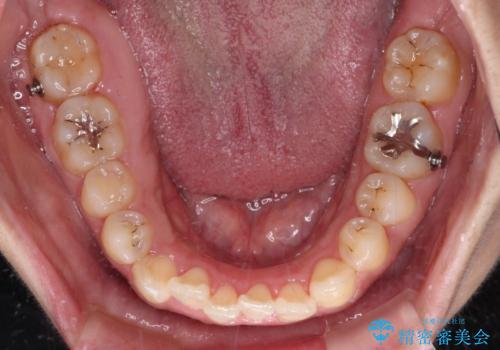

- 前歯の叢生と八重歯を気にして来院された患者様です。

目立たない装置を希望とのことで、インビザラインにて矯正治療を行うこととしました。

インビザライン単体で改善することも可能ですが、八重歯とその後方にある歯列を確実移動させないと、上下正中がずれてしまう可能性があります。

インビザライン単体での治療ではなく、カリエール・ディスタライザーという補助装置を併用して、より確実性を上げることとしました。

補助装置で八重歯を解消しながら、並行してインビザラインで歯列を整えることとしました。